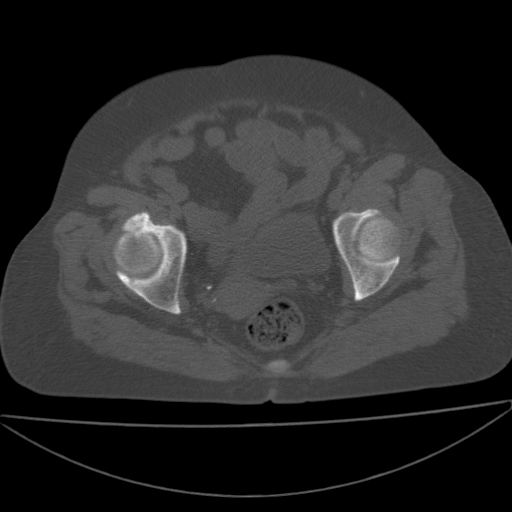

以下是引用王显瑞在2009-4-23 16:45:00的发言:[br]考虑股骨颈陈旧性骨折,股骨头缺血型坏死

以下是引用余辉在2009-4-23 17:08:00的发言:[br]考虑右髋关节退行性变.股骨颈改变考虑陈旧性骨折可能,股骨头顶部关节面下似有透亮区,股骨头皮质环增厚,考虑有股骨头坏死